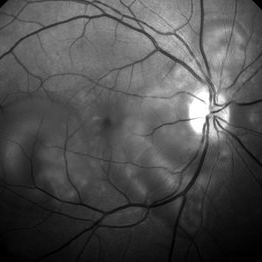

Preeclampsia in a 30-Year-Old - Red Free Photograph - RE

Nov 25 2015 by Roy Schwartz, MD

A 30-year-old presented with central scotoma and blurred vision a day following C-section for preeclampsia.

Photographer: Galit Yair Pur

Condition/keywords: blurred vision, central scotoma, preeclampsia